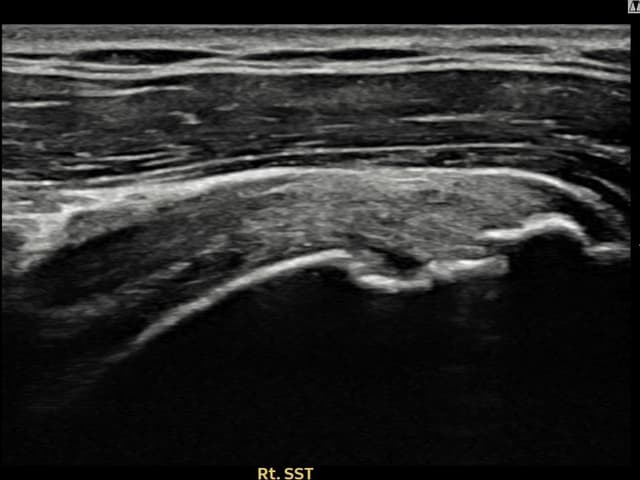

[経過期間: 23.10.05~23.12.07]

[縫縮術] 超音波検査にて右 棘上筋腱 付着部部分断裂(10mm × 4mm (腱厚の約42%欠損))を確認。縫縮術施行後、腱の連続性が回復し、日常生活に復帰されました。